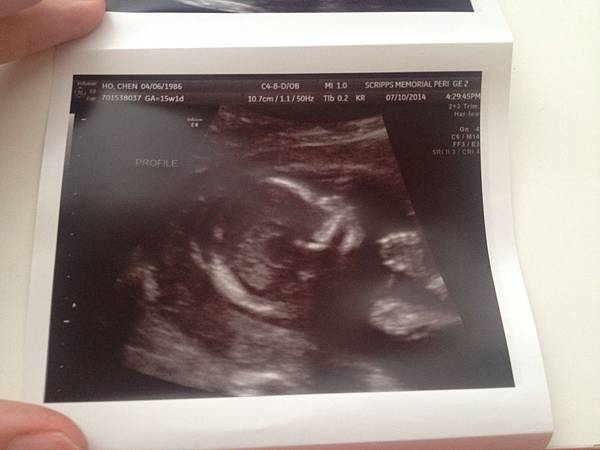

這是寶寶的側臉喔 看起來蠻清楚的耶 ((九妞妞:到底是清楚在哪 這種照片只有當媽的人看得懂吧XD))

當超音波停格在寶寶的側臉的時候 媽媽很興奮的問超音波師 那個凸起來的是他的鼻子嗎?

她說是的!

媽媽開心的都要灑花了 懷孕的時候就一直叮嚀寶寶要遺傳到爸媽的挺鼻子

超音波看起來是蠻挺的

僑哥注意的是他的頭型 因為僑哥深受扁頭所苦 所以他看到寶寶的側面 開心的說:看起來頭型蠻圓的